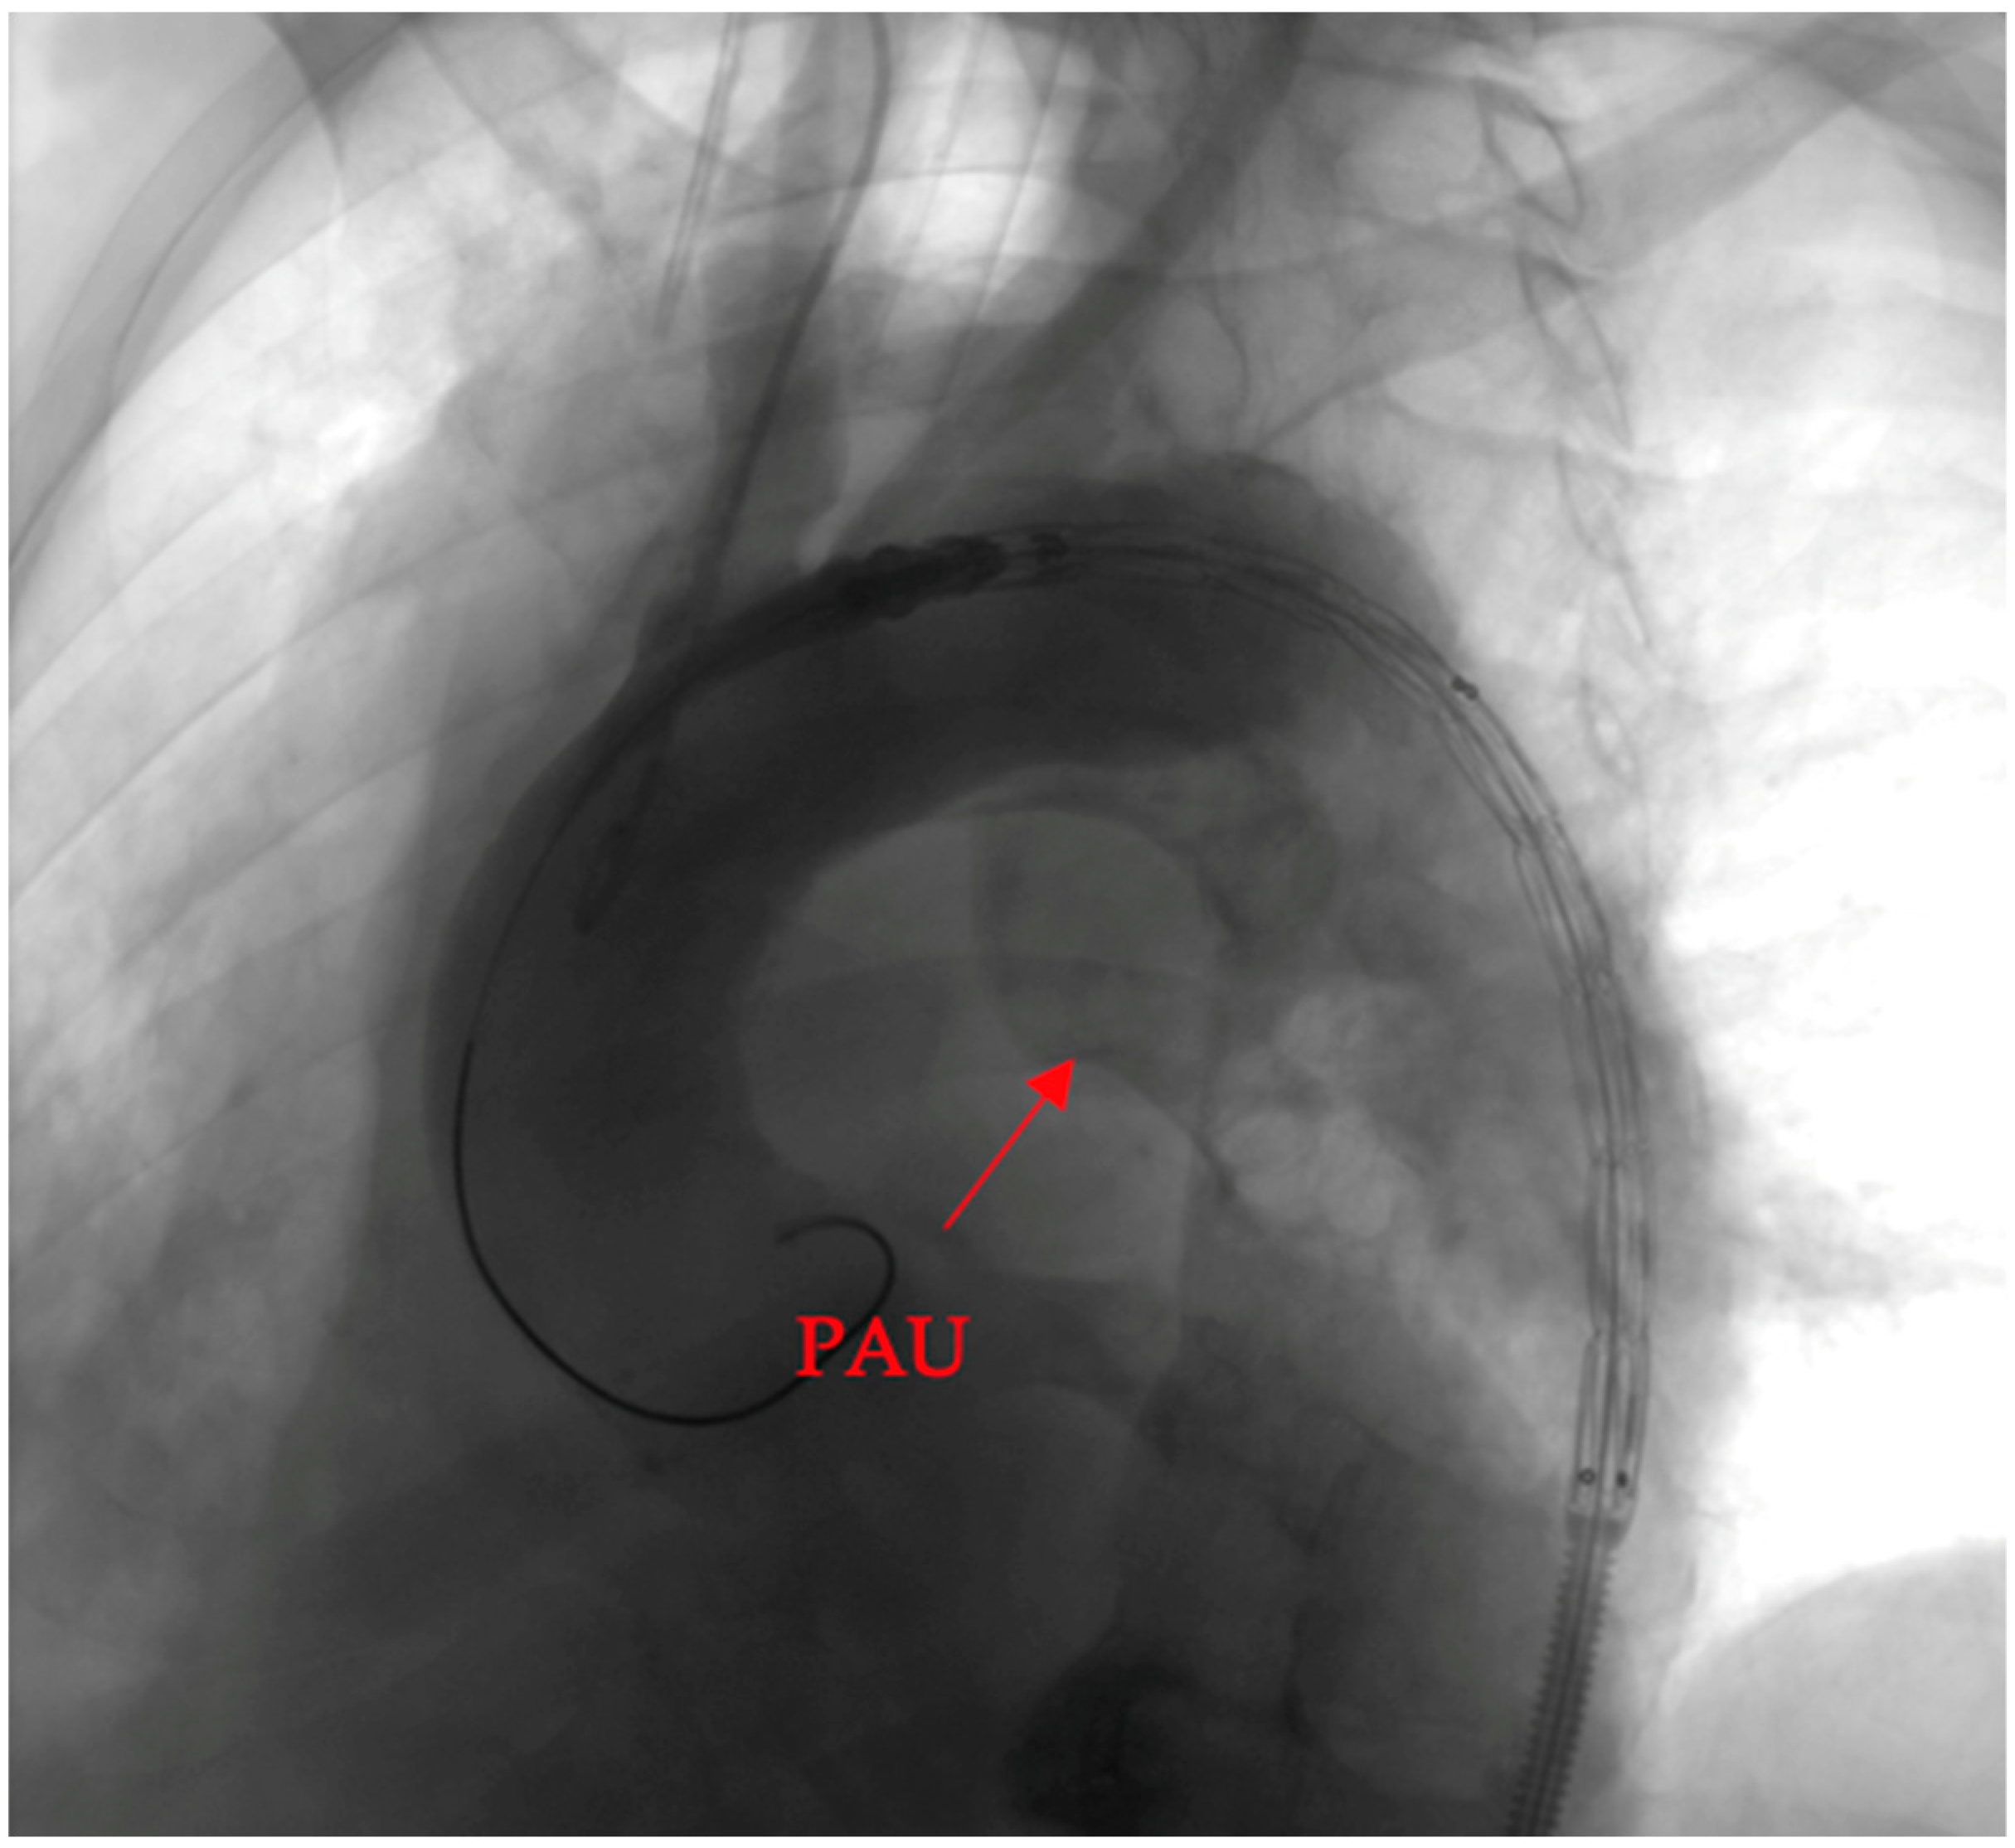

- Penetrating aortic ulcer ruptured: As seen in Figure 2, the thoracic angio-CT scan identified a penetrating ulcer within the aortic wall, particularly located in the isthmic region, measuring approximately 4.2 cm × 3.5 cm. This was a concealed source of significant concern, as it posed an imminent risk of catastrophic hemorrhage.

- Right pleural aortic false aneurysm (Figure 3): The most striking feature was the presence of an expansive false aneurysm within the right pleural cavity, measuring approximately 12.92 cm × 9.3 cm. The size and location of this pseudoaneurysm were unprecedented, introducing a challenge in terms of diagnosis and intervention.